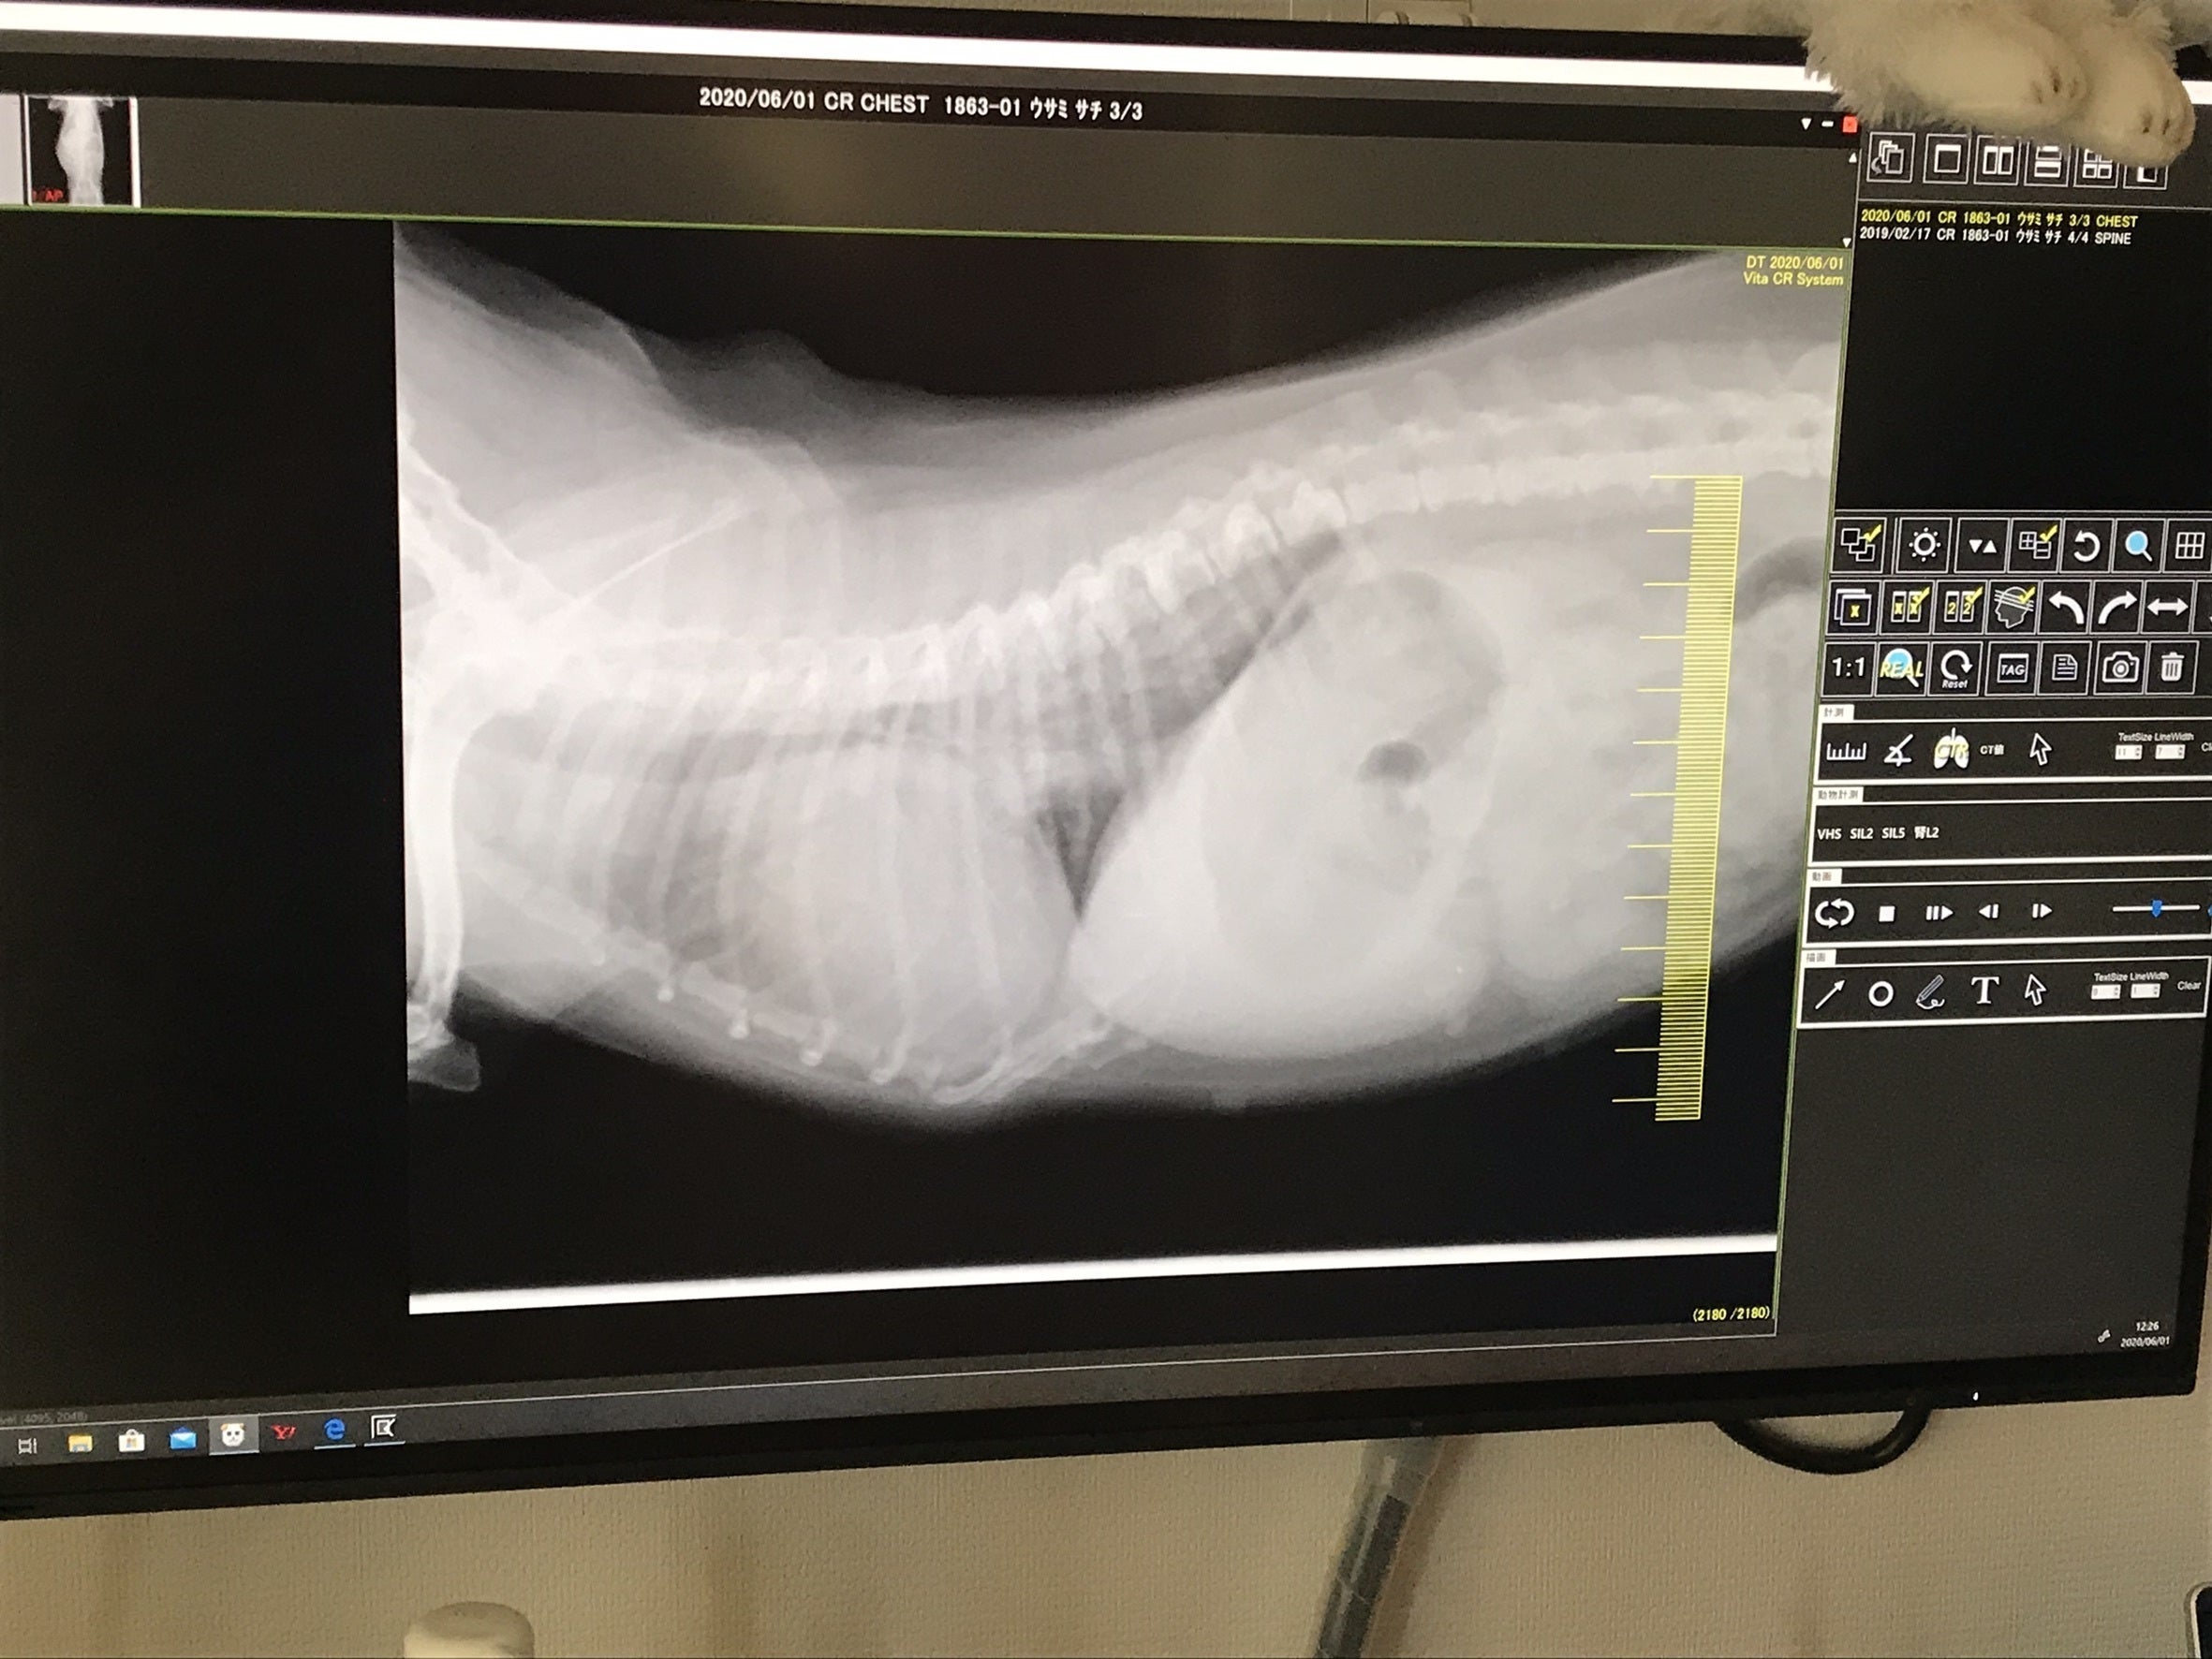

2020/6/1 初診

身体検査、血液検査、レントゲン撮影、酸素室治療を致しました。

この時点で心臓病と診断されました。

次はレントゲン写真です。心臓が肥大して肺を圧迫しております。血液が逆流するため心臓により大きい負担がかかり、心不全や肺水腫などを引き起こします。この時点で肺水腫を起こし肺に水が溜まっておりました。